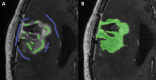

Background: The current method for assessing progressive disease (PD) in glioblastoma is according to the Response Assessment in Neuro-Oncology (RANO) criteria. Bevacizumab-treated patients may show pseudo-response on postcontrast T1-weighted (T1w) MRI, and a more infiltrative non-enhancing growth pattern on T2w/fluid attenuated inversion recovery (FLAIR) images. We investigated whether the RANO criteria remain the method of choice for assessing bevacizumab-treated recurrent glioblastoma when compared with various volumetric methods.

Methods: Patients with assessable MRI data from the BELOB trial (n = 148) were included. Patients were treated with bevacizumab, lomustine, or both. At first and second radiological follow-up (6 and 12 wk), PD was determined using the 2D RANO criteria and various volumetric methods based on enhancing tumor only and enhancing plus non-enhancing tumor. Differences in overall survival (OS) between PD and non-PD patients were assessed with the log-rank test and a Cox model. Hazard ratios (HRs) and their 95% CIs were determined.